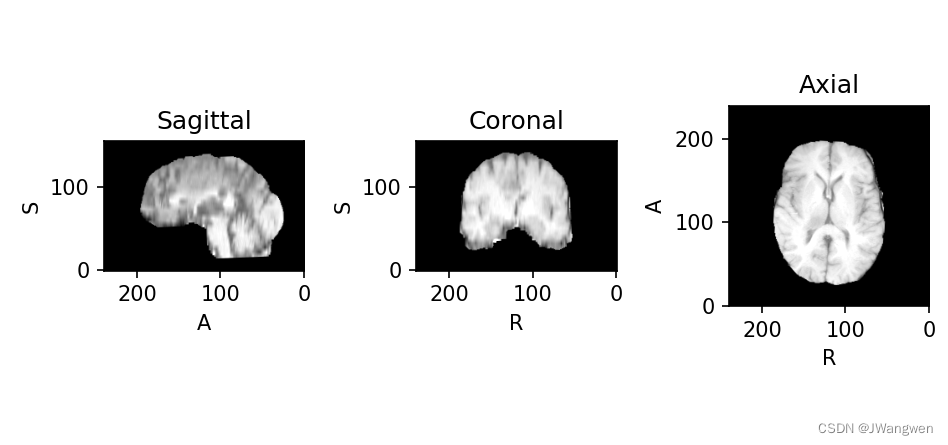

读取文件并显示图片(以下仅读取t1):

import torchio as tio

t1_path = 'BraTS19_2013_2_1_t1.nii.gz'

t1_img = tio.ScalarImage(t1_path)

t1_img.plot()

t1显示如下: